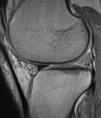

En la RM, el implante meniscal era del mismo tamaño que el menisco normal (tipo 3) en 5 de los pacientes un año después de la cirugía (fig. 2), pero al final del seguimiento el tamaño había disminuido en todos los pacientes. En ninguno de los casos la morfología se clasificó como de tipo 1, ya sea a los seis meses, doce meses o en el seguimiento final. La intensidad de la señal de RM disminuyó progresivamente pero no llegó a ser en ninguno de los casos igual a la de un menisco normal.

En uno de los pacientes, el de mayor edad y con peor evolución, la RM mostró dos años después de la cirugía extrusión del implante con una morfología de tipo 2 y un tipo de señal 1 (fig. 3). Se realizó una artroscopia debido a la persistencia del dolor observándose una progresión de los cambios degenerativos del cartílago del cóndilo medial (ICRS 3). El implante se hallaba completamente integrado con el cuerno anterior del menisco, con una morfología similar a la de un menisco normal en este área (fig. 4A), pero en su zona posterior mostraba fibrilación y rotura, con un color amarillento (fig. 4B). La biopsia realizada en la zona media del implante mostró la presencia de fibrocartílago con características similares a la de los menisco normales en la hematoxilina y eosina (fig. 5). El implante se dejó in situ y se retiraron las suturas que eran visibles.